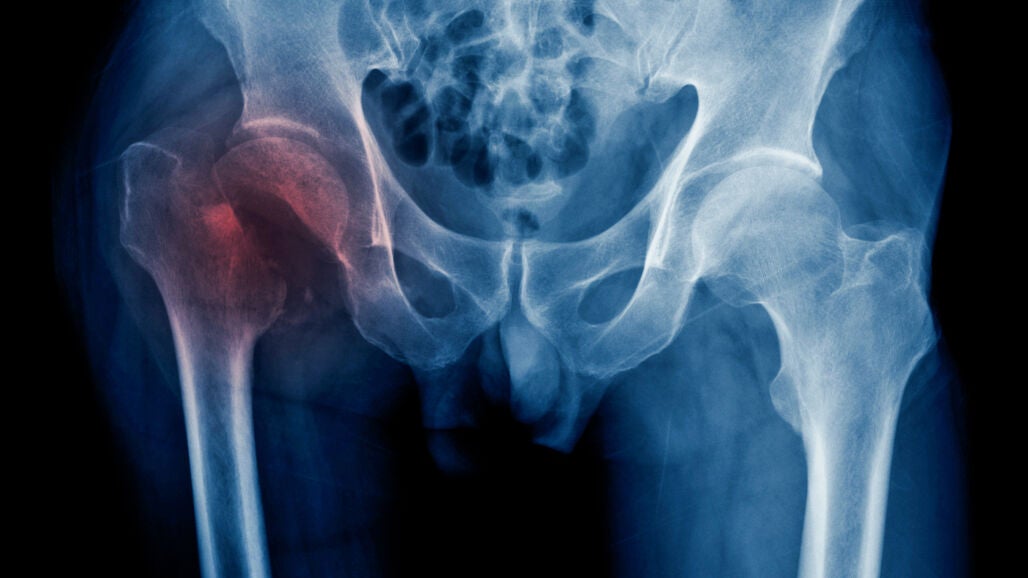

Las fracturas de cadera tienen más riesgo de desencadenar eventos cardiovasculares adversos

Un estudio ha hallado que la insuficiencia cardíaca o el infarto de miocardio tienen un mayor riesgo de aparecer tras una fractura de cadera. Este descubrimiento puede facilitar la introducción de tratamientos personalizados para los pacientes con fractura de cadera.

Un equipo de investigación del Departamento de Farmacología y Farmacia de la Facultad de Medicina de Hong Kong (China) ha descubierto que las fracturas de cadera pueden desencadenar eventos cardiovasculares adversos, y que aquellos pacientes con afecciones cardíacas preexistentes tienen cinco veces más riesgo de sufrir este tipo de eventos, lo que se traduce en un peor pronóstico y un mayor uso de los servicios sanitarios.

El estudio, publicado en la revista Nature Communications, muestra que eventos como la insuficiencia cardíaca o el infarto de miocardio tienen un mayor riesgo de aparecer tras una fractura de cadera, y en el que los científicos han registrado "una notable falta de énfasis" en su manejo.